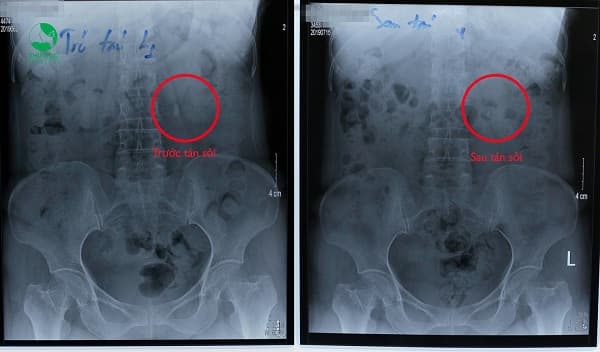

- Phim chụp trước – sau khi tán sỏi ngoài cơ thể, sỏi đã sạch chỉ sau 1 lần tán.

Anh N.V. Phú (41 tuổi, Hà Nội) đi khám sau một thời gian thấy đau nhiều vùng thắt lưng. “Bác sĩ xem phim chụp bảo hai bên đều có sỏi to, xấp xỉ 10mm. Trước đó đã từng mổ một lần rồi nên tôi sợ lắm, cứ nghĩ lần này mà phải mổ tiếp nữa thì…” Vì thế khi được bác sĩ giới thiệu về phương pháp tán sỏi ngoài cơ thể không hề động dao kéo, không đau, anh rất mừng. Sau 2 lần tán sỏi ngoài cơ thể, với mỗi lần tán 1 viên sỏi ở mỗi bên thận, các mảnh sỏi vụn sau khi tán được đào thải ra ngoài qua đường nước tiểu. Khi tái khám tại bệnh viện vào 10 ngày sau, thận của anh Phú đã không còn dấu hiệu của sỏi.